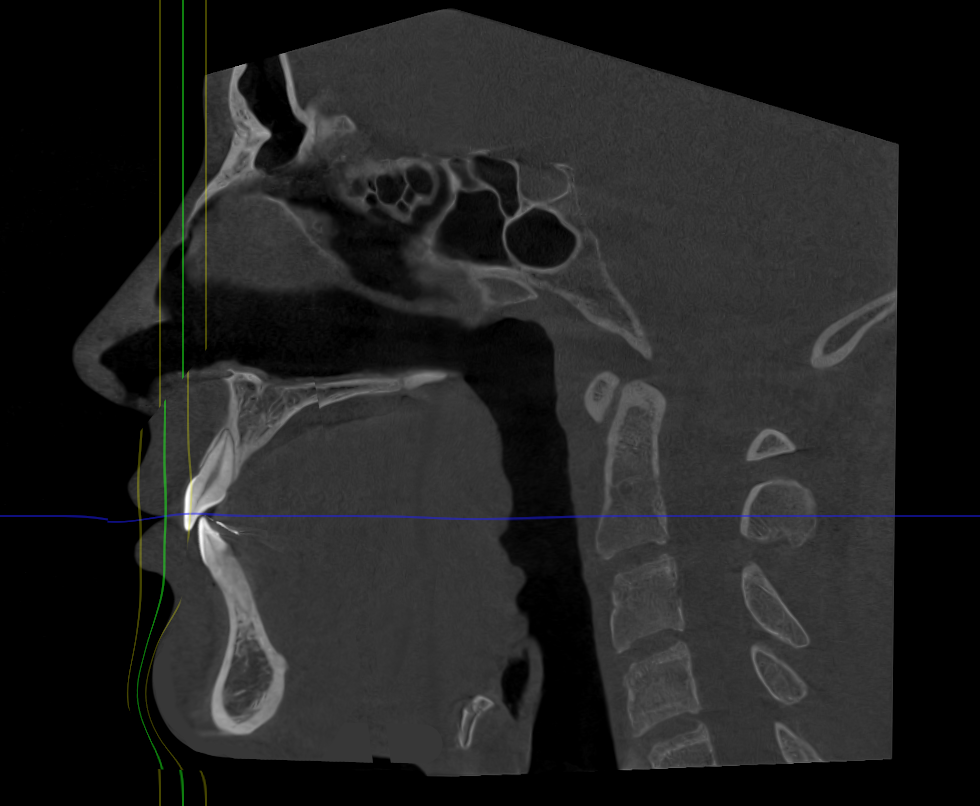

I played with my cbct a bit and this is something close to what I'm going to get.

4.4mm on maxilla and approx. 15mm on the lower

However, to pass all the convexities in a chad tier i would need 8.8mm on maxilla and 20mm on my lower jaw (likely 12/13mm lj + 8/7mm genio)

Of course, im also getting some counter clockwise rotation